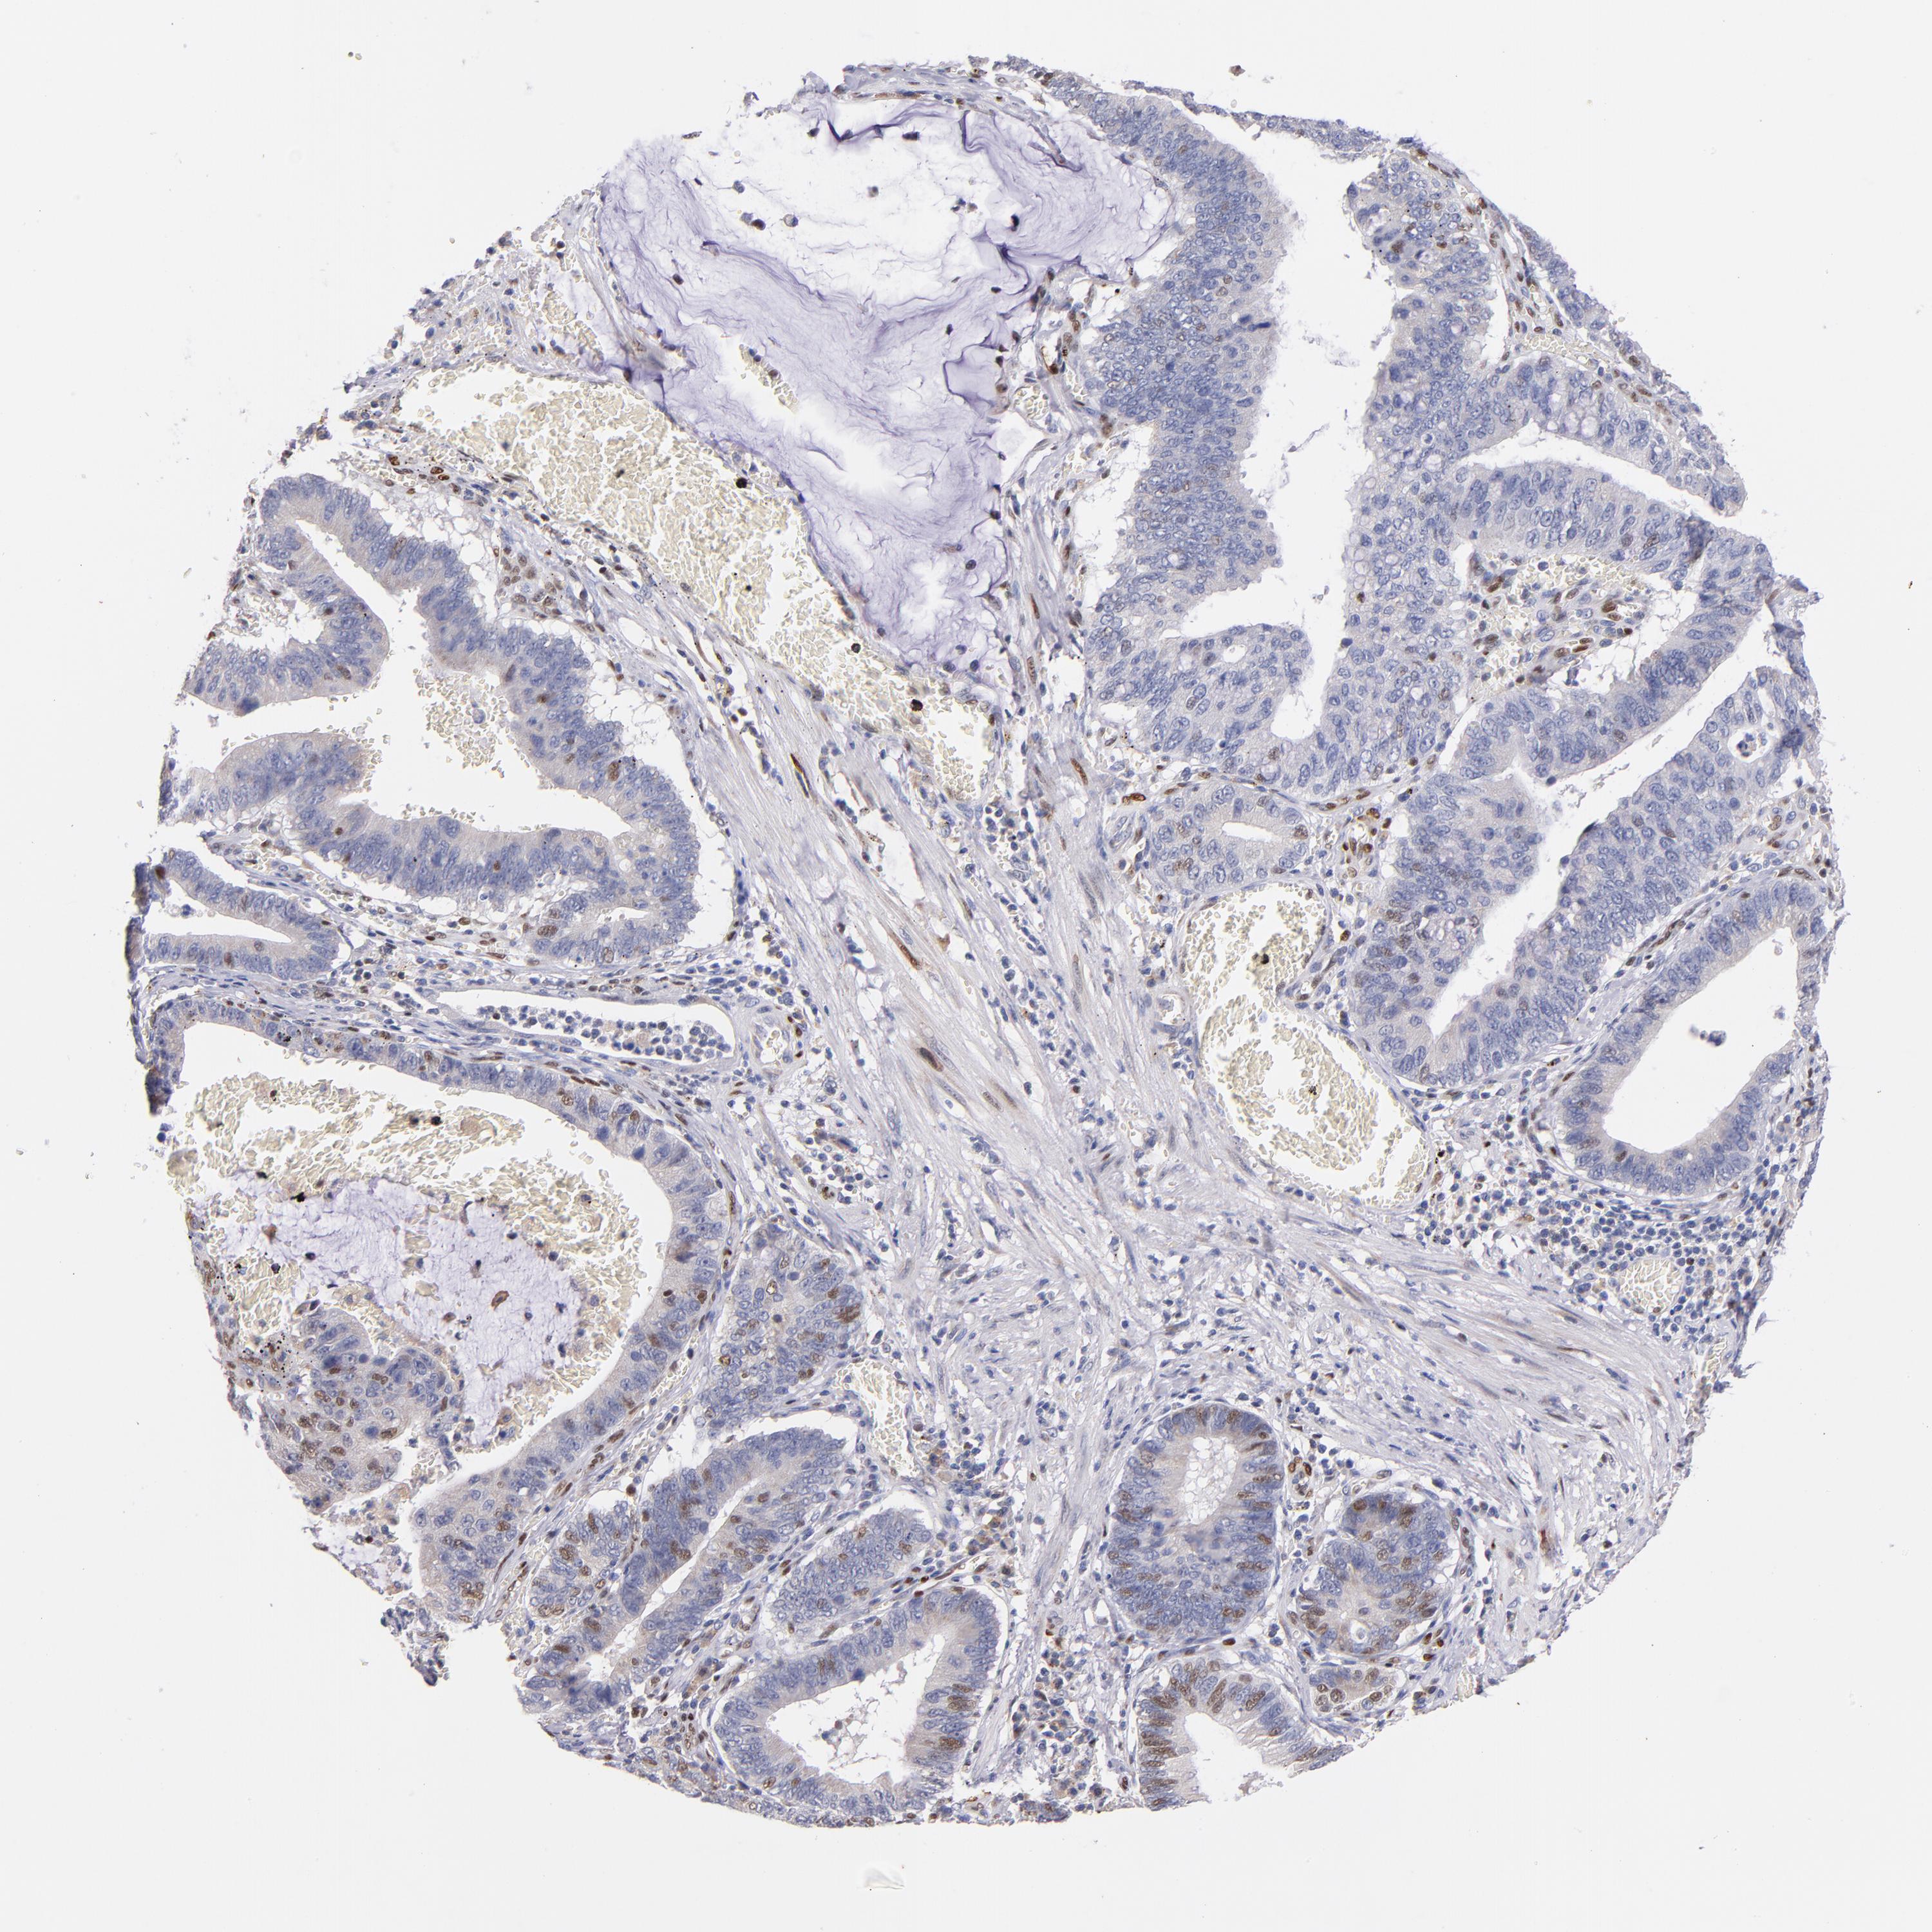

STOMACH CANCER - Protein expressioni

A mouse-over function shows sample information and annotation data. Click on an image to view it in a full screen mode. Samples can be filtered based on level of antibody staining by selecting one or several of the following categories: high, medium, low and not detected. The assay and annotation is described here.

Note that samples used for immunohistochemistry by the Human Protein Atlas do not correspond to samples in the TCGA dataset.

Antibody stainingi

Antibody staining in the annotated cell types in the current human tissue is reported as not detected, low, medium, or high, based on conventional immunohistochemistry profiling in selected tissues. This score is based on the combination of the staining intensity and fraction of stained cells.

Each image is clickable and will lead to virtual microscopy that enables deeper exploration of all samples and also displays staining intensity scores, fraction scores and subcellular localization as well as patient and tissue information for each sample.

Antibody HPA001819

Antibody CAB005416

Staining

High

Medium

Low

Not detected

Intensity

Strong

Moderate

Weak

Negative

Quantity

>75%

75%-25%

<25%

None

Location

Nuclear

Cytoplasmic/membranous

Cytoplasmic/membranous,nuclear

Adenocarcinoma, NOS

Adenocarcinoma, High grade